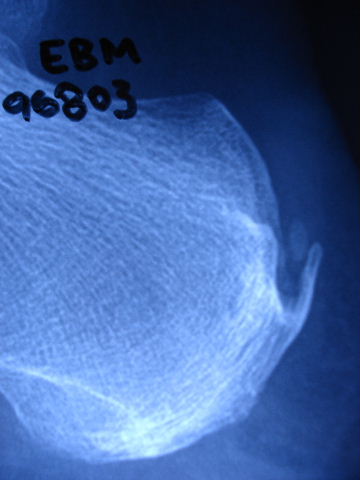

Fractura impactada de húmero .

Fractura de húmero, intensa desviación de fragmentos

Fractura de húmero.

Fractura compleja de húmero.